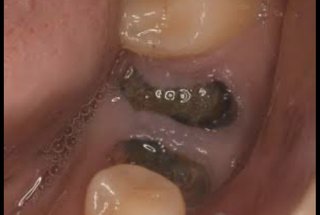

歯医者について、お話聞いてもらえませんか? 投稿画像

歯医者について、お話聞いてもらえませんか?